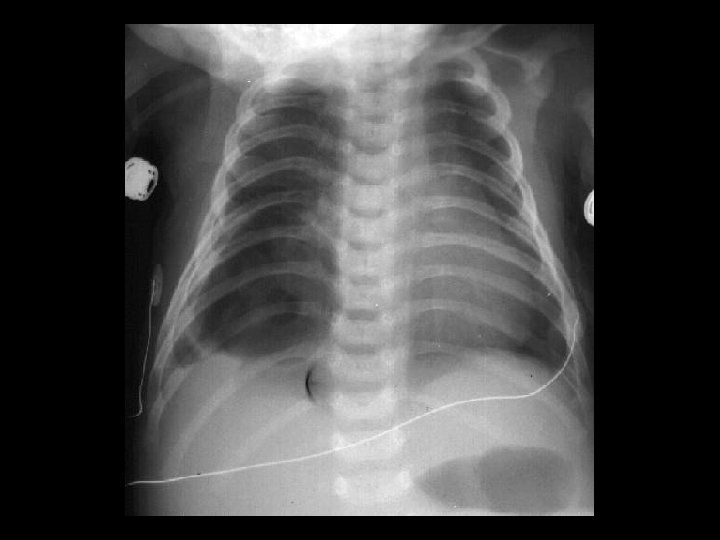

Hyaline Membrane Disease (HMD) • Findings: – symmetric, homogeneous “ground glass” appearance – air-bronchograms – decreased lung volumes • Pre-term infants with sufactant deficiency • generalized capillary leak • ddx: – neonatal pneumonia – transient tachypnea of the newborn – meconium aspiration